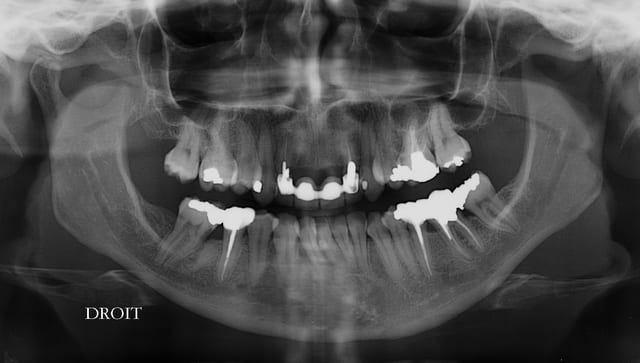

Patiente sympa, 30 ans, un bridge ceramo-métal fait il y a 10 ans, en fin de vie.

En réalité je sais déjà ce que je vais faire, mais implants, bridge ou pourquoi pas adjointe???

Les endo et les IC dans les 12-22 sont sublimes...et ça a durer 10 ans....incroyable...Il y a pas de la paro aussi ?

étonnant en effet... et encore plus étonnant, ce qui n'arrive jamais le radiologue (qui est parfaitement compétent normalement) a inversé la droite et la gauche.

Oui et un peu particulier au niveau de 12/22, le bridge a été fait suite à un accident sur 11/21, mais soit l'accident était grave, soit le confrère Marocain, un peu pressé.

Ceci a d’ailleurs guidé mes choix, qui ne sont pas forcement évidents, mais Primum non nocere... enfin pas plus que ce qui est déjà fait.